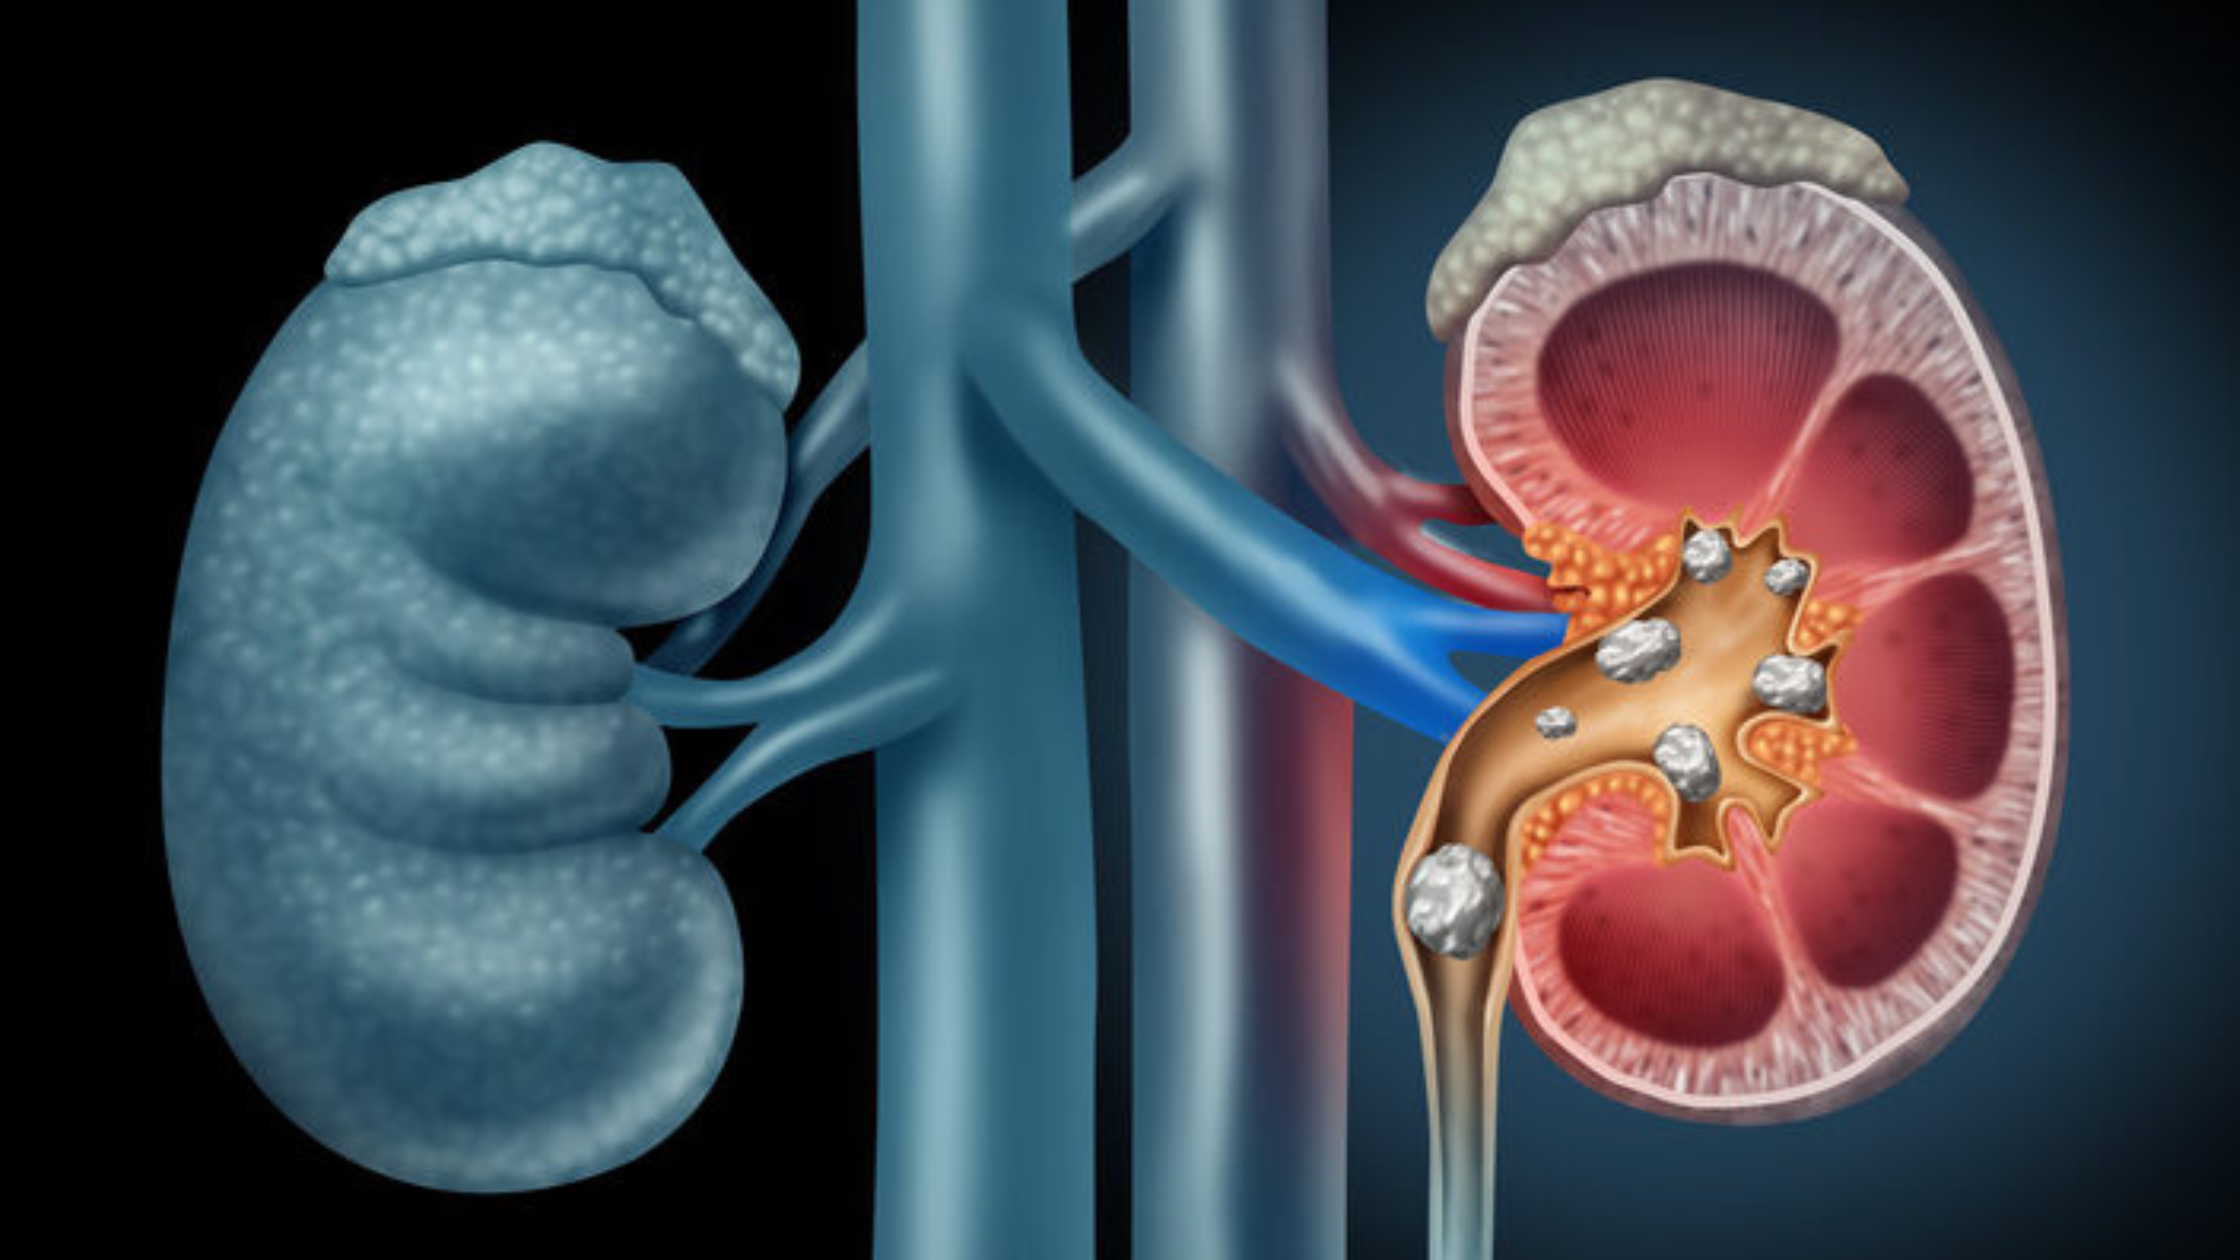

Kidney stones, though diminutive in size, wield the power to unleash intense waves of pain and discomfort. As these crystalline formations obstruct the urinary tract, those who suffer from them […]

Kidney stones, though diminutive in size, wield the power to unleash intense waves of pain and discomfort. As these crystalline formations obstruct the urinary tract, those who suffer from them […]

Kidney stones can bring about excruciating pain and discomfort, affecting millions of individuals globally. When these stubborn stones refuse to pass naturally or grow too large to be managed with […]